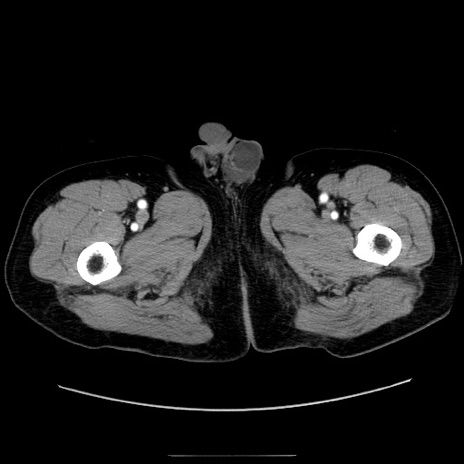

症例30(横断像)

【症例】80歳代男性

【主訴】臍周囲痛

【現病歴】約6時間前から臍下部痛が出現。次第に腹部膨隆・背部痛も生じてきたため来院。背部痛の場所は変化しない。

【身体所見】意識清明、BT 36.3℃、BP  131/87mmHg、P 87bpm、SpO2 100%(RA)、臍周囲自発痛・圧痛あり、反跳痛なし、自発痛部位に一致して板状硬あり、腹部膨隆、腸雑音減弱、CVA tenderness両側陰性。